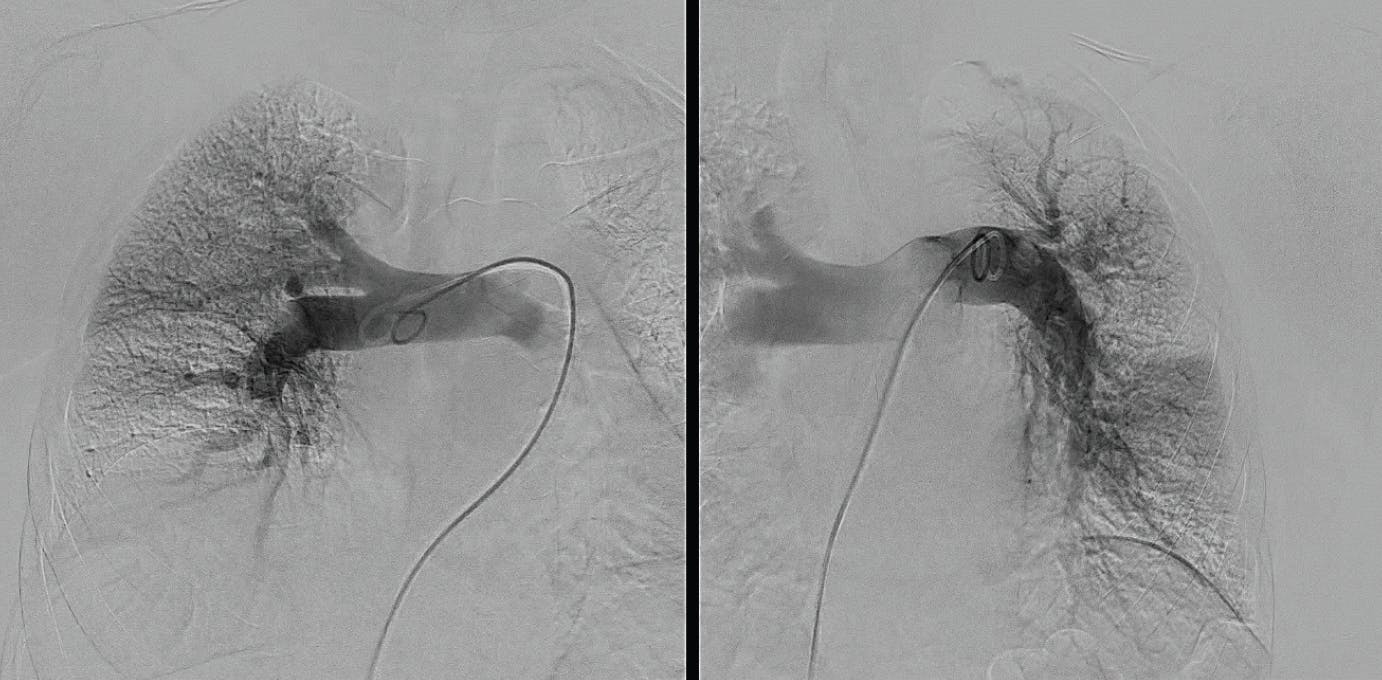

Figure 1. Right initial angiogram.

Figure 2. Left initial angiogram.

Based on the evaluation, the decision was made to pursue aspiration thrombectomy using the Lightning Flash device. The opening PA pressures were 33/12 mm Hg (mean, 20 mm Hg) and closed with 18/3 mm Hg (mean, 8 mm Hg), taken through the 16-F, 65-cm Gore DrySeal sheath, showing a significant drop in pressure. The device time of Lightning Flash was 6 minutes, and the total procedure time was 55 minutes (Figure 3, Figure 4, and Figure 5). By the conclusion of the case, the EBL was 100 mL and postprocedure BP was 122/63 mm Hg, HR was 54 bpm, and oxygen saturation was 97% on 2 L nasal cannula.

Figure 3. Right post-thrombectomy angiogram.

Figure 4. Left post-thrombectomy angiogram.